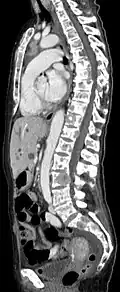

Computertomografie

Die Computertomografie (CT) erfolgt meist nach der konventionellen Röntgenaufnahme und der Skelettszintigrafie. In diesen der CT vorgeschalteten Untersuchungsverfahren werden die Bereiche lokalisiert, die dann mittels CT in erheblich höherer Auflösung und besserer Qualität dargestellt werden sollen. Die CT liefert Informationen über das Ausmaß der Knochenzerstörung und die Stabilität des von Knochenmetastasen betroffenen Bereiches.[85] Diese Informationen sind für die Planung der Behandlung, insbesondere für etwaige chirurgische Interventionen, von großer Wichtigkeit.

Die Indikation für eine CT ist daher vor stabilisierenden operativen Eingriffen (beispielsweise eines Wirbelsäulenabschnittes), vor einer Nadelbiopsie (wenn die Läsion im Szintigramm sichtbar, aber in der Röntgenaufnahme nicht sichtbar ist) sowie bei drohenden oder bereits eingetretenen Frakturen gegeben.[85]

- Vergleich CT / MRT bei osteolytischen Metastasen eines Mammakarzinoms in der Wirbelsäule

-

Sagittal rekonstruierte CT, Darstellung im Knochenfenster. Da die Patientin multiple Metastasen in allen Körperregionen hatte, konnte sie die Arme nicht für die Untersuchung nach oben nehmen, weshalb die Hände mit abgebildet sind. -

Sagittal rekonstruierte CT, Weichteilfenster. Neben den Metastasen in der Wirbelsäule, die teilweise nach hinten in den Spinalkanal einwachsen, auch Metastasen im Brustbein. Zusätzlich Lebermetastasen. -